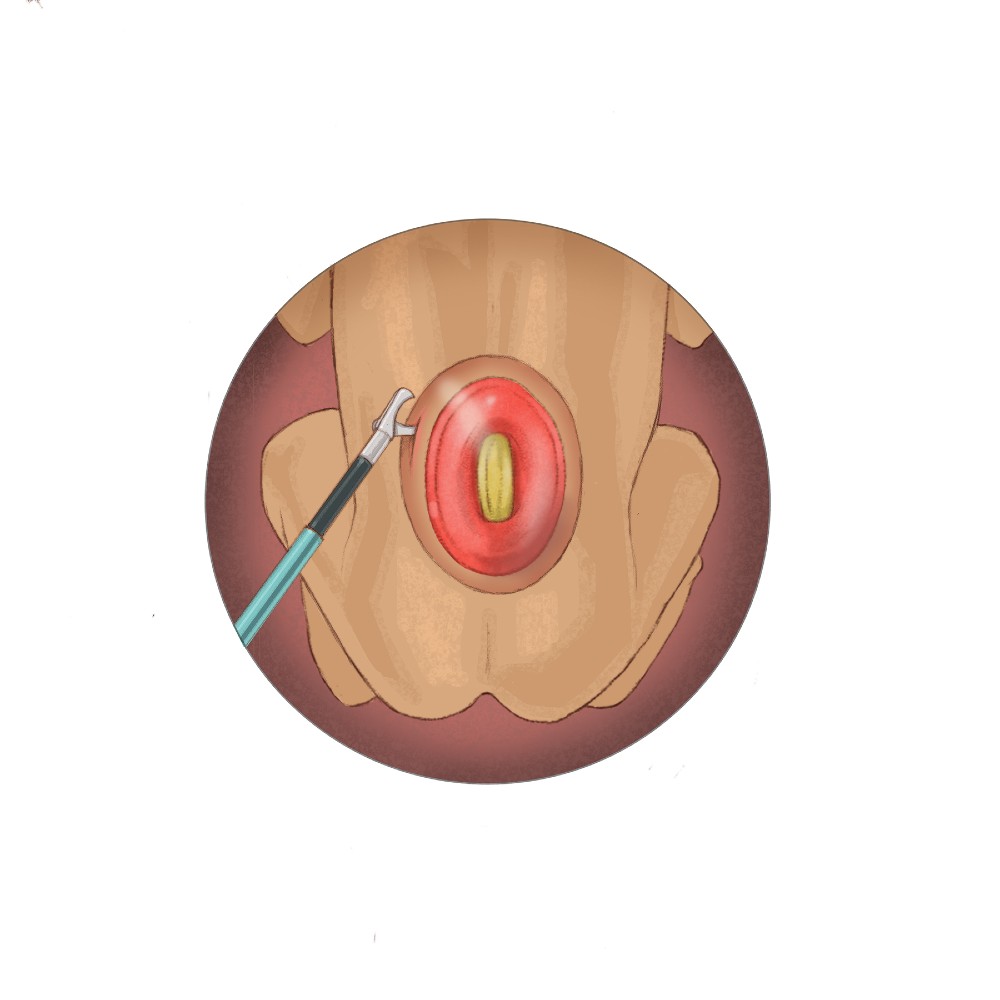

“Our primary outcome measure for the study is successful surgical closure of the spina bifida defect with a watertight patch that approximates native tissue and allows for the natural growth of the spinal cord,” Dr. Papanna says. “The procedure differs from in-utero repair, which requires a large incision on the uterus and delivery by cesarean section. Instead, we will repair the spina bifida defect in two layers through three small incisions in the uterus using fetoscopes and tiny surgical tools. The first layer will be closed using a NEOX®Cord 1K patch as a meningeal patch placed over the spinal cord, followed by a second layer of primary closure of the skin. Mothers will undergo vaginal delivery, unless there is an obstetrical indication for delivery by C-section.”

The NEOX Cord 1K patch is made of cryopreserved umbilical cord and amniotic membrane. Extensive laboratory and clinical research on an ocular wound surface has shown that placental tissues help manage inflammation in wounds, facilitate cell proliferation and create an environment for tissue regeneration. NEOX Cord 1K has demonstrated consistently high closure rates in real-world experiences.